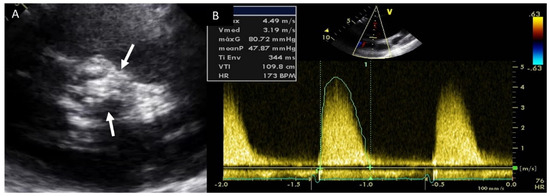

4.2. Aortic Stenosis

- Shen, M.; Tastet, L.; Capoulade, R.; Arsenault, M.; Bédard, É.; Clavel, M.-A.; Pibarot, P. Effect of bicuspid aortic valve phenotype on progression of aortic stenosis. Eur. Heart J. Cardiovasc. Imaging 2020, 21, 727–734. [Google Scholar] [CrossRef]

- Yang, L.-T.; Boler, A.; Medina-Inojosa, J.R.; Scott, C.G.; Maurer, M.J.; Eleid, M.F.; Enriquez-Sarano, M.; Tribouilloy, C.; Michelena, H.I. Aortic Stenosis Progression, Cardiac Damage, and Survival: Comparison Between Bicuspid and Tricuspid Aortic Valves. JACC Cardiovasc. Imaging 2021, 14, 1113–1126. [Google Scholar] [CrossRef] [PubMed]

- Beppu, S.; Suzuki, S.; Matsuda, H.; Ohmori, F.; Nagata, S.; Miyatake, K. Rapidity of progression of aortic stenosis in patients with congenital bicuspid aortic valves. Am. J. Cardiol. 1993, 71, 322–327. [Google Scholar] [CrossRef]

- Michelena, H.I.; Margaryan, E.; Miller, F.A.; Eleid, M.; Maalouf, J.; Suri, R.; Messika-Zeitoun, D.; Pellikka, P.A.; Enriquez-Sarano, M. Inconsistent echocardiographic grading of aortic stenosis: Is the left ventricular outflow tract important? Heart 2013, 99, 921–931. [Google Scholar] [CrossRef]